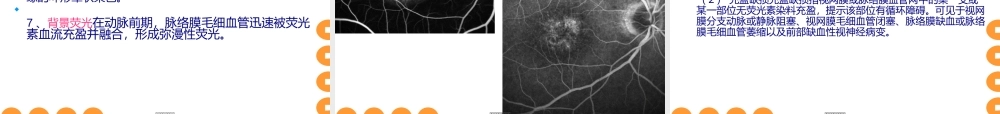

荧光素眼底血管造影(FFA)是当代眼科(yǎnkē)诊断眼底病常见重要的检查方法之一。对眼底病的诊断、鉴别诊断、治疗选择、预后的推断都具有重要意义。第第第第第第第第第第第第第第第第第第第第眼底荧光血管造影的原理操作方法异常(yìcháng)荧光图象的表现。第第第第第第第第第第第第第第第第第第第第荧光素钠又称荧光红、荧光黄,是大量荧光物质中最富有荧光特性的化合物。其分子式C20H10O5Na2,分子量为376.27(Dalton)。在自然界,某些化合物受光线照射后,吸收辐射光的部分能量,并可发射(fāshè)出不同于原有波长的光线。当光线停止照射后,被照射的化合物发射(fāshè)的光线在9-10秒内停止者,称为荧光。用于血管造影的荧光素是一种染料,一般以钠盐的形式存在,即荧光素钠。荧光是一种电子现象,主要受波长200~800nm光线的作用。眼底荧光血管造影时,眼底血管中循行的荧光素吸收波长被490nm的蓝光激发后,发射出波长520nm的绿光。人们根据荧光素的这种吸收和发射光谱的差异作为荧光造影机滤光片选择和组合的依据。第第第第第第第第第第第第第第第第第第第第眼底荧光血管造影(fundusfluoresceinangiography,FFA),是将荧光素钠荧光素钠作造影剂从肘静脉注入,利用特定组合的滤光片和眼底照相机,观察并连续拍摄眼底血管中荧光素循行时吸收激光后所发射出的荧光,是主要反映视网膜血管及灌注状况的一种重要诊断技术。该技术的特点是将眼底检查从眼底镜下静态的形态学观察转变为动态的循环动力学研究,使眼底病的诊断方法由主观检查转变为可提供客观依据的科学(kēxué)鉴定。眼底荧光血管造影的检查结果可为临床医生提供眼底病诊断和治疗的客观指标。第第第第第第第第第第第第第第第第第第第第1、传统(chuántǒng)眼底照相机常用的有CANON,TOPCON,NIKON,ZEISS,KOWA等。2、激光扫描检眼镜(ScanningLaserOphthalmoscope,SLO)3、共焦激光扫描(检眼镜)系统(CSLO)共焦激光扫描(检眼镜)系统(CSLO)其中海德堡视网膜血管造影Ⅱ(HeidelbergRetinaAngiography2,HRA-Ⅱ)海德堡视网膜血管造影Ⅱ(HeidelbergRetinaAngiography2,HRA-Ⅱ)比较常用。第第第第第第第第第第第第第第第第第第第第KOWATOPCON第第第第第第第第第第第第第第第第第第第第CANON第第第第第第第第第第第第第第第第第第第第海德堡HRA第第第第第第第第第第第第第第第第第第第第现代眼底荧光造影使用数码图象处理系统进行血管造影...